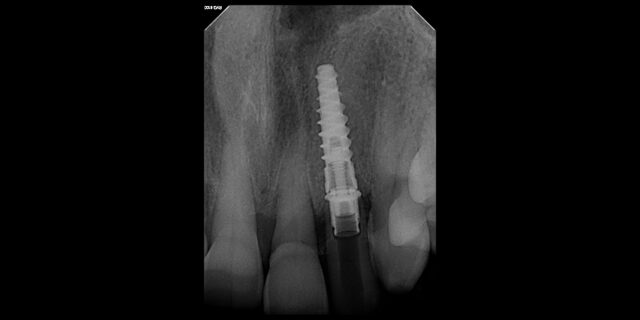

• We all can agree you want a minimum of 1.5 between implant and tooth. What are the risks if it is 1.2 or 1.0. Are they ways to still have success?

Attached is a picture of an immediate implant placement after extraction, threading the needle. In the picture we had 1.5 mm but I know posts with pictures do better lol.

• Yes, typically you want 1.5mm to 2 millimeters between tooth and implant however, sometimes in cases where it’s tight, we can’t achieve that. One possible complication can be bone loss overtime, or just rejection of the implant due to lack of blood supply. However, over many cases I have been much less than that with good outcomes, especially…

Read more